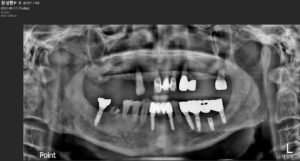

정밀한 검사를 위해

파노라마 사진을 촬영해 보았더니

위턱 잔존 치아들 주변으로

잇몸뼈 흡수가 심하고

염증이 있는 상태로

예후가 좋지 않아

발치가 불가피한 상황이었으며,

아래턱 오른쪽 뿌리만 남은 치아 역시

발치가 불가피하였는데요.